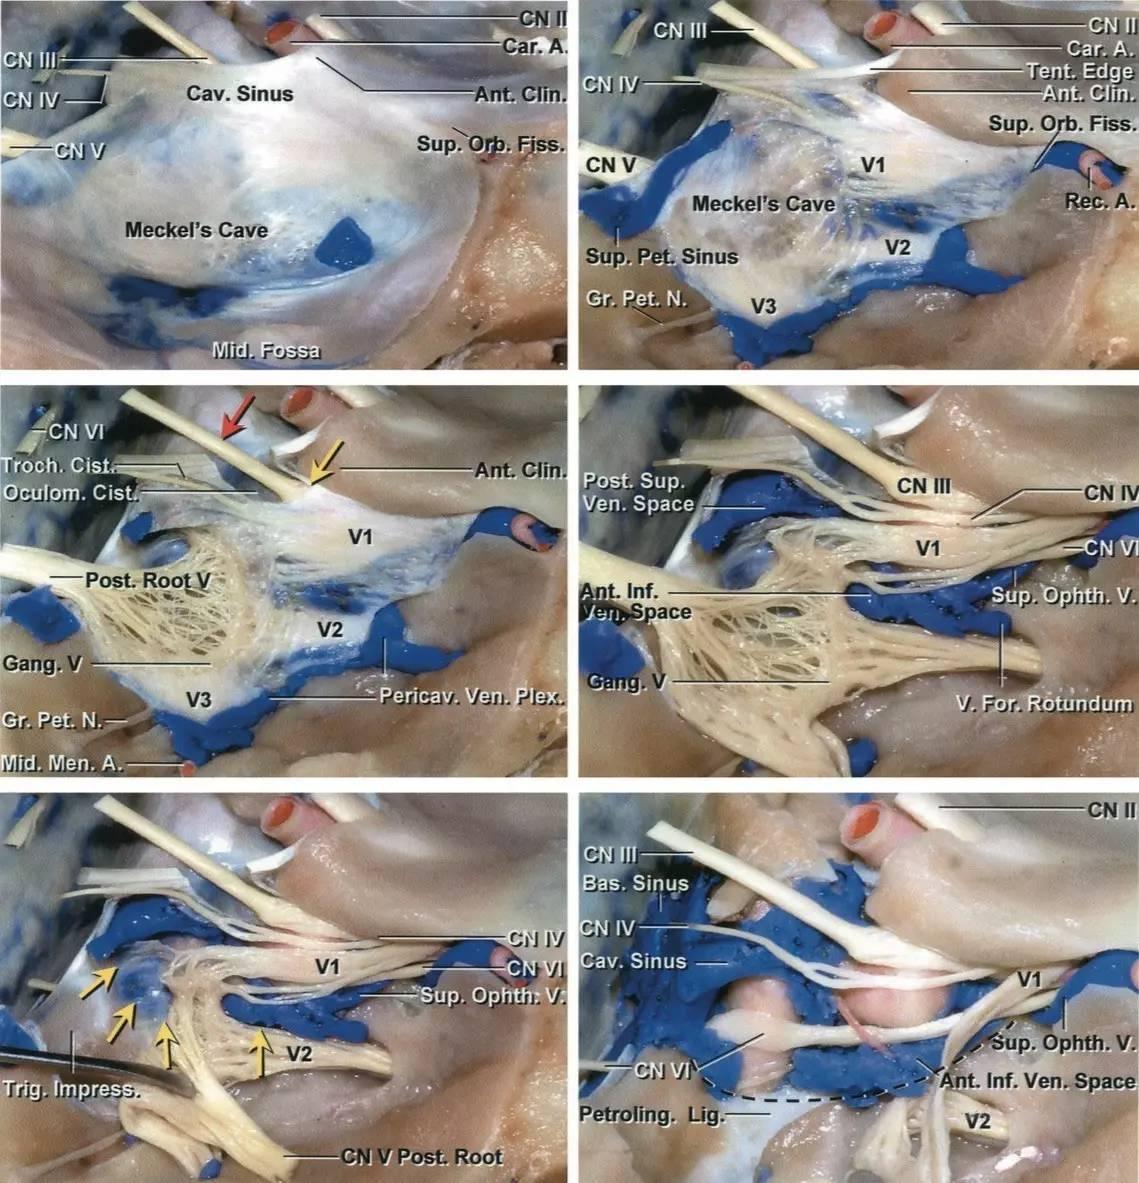

图2:逐层分步解剖右侧海绵窦。海绵窦外侧壁内走行有动眼神经、滑车神经、三叉神经眼支和上颌支(Rhoton教授原图认为上颌支位于海绵窦以外,译者注),外展神经则紧贴颈内动脉行于海绵窦内部(左上图)。剥开覆盖颞叶的外层脑膜层(即海绵窦外侧壁的外层,译者注),可见动眼神经和滑车神经进入海绵窦顶壁,并前行进入眶上裂(右上图)。动眼神经在海绵窦顶壁行于一小段蛛网膜池中(红色箭头),直至前床突下缘时才进入海绵窦侧壁(黄色箭头,左中图)。剥除海绵窦外侧壁的残余硬膜(外侧壁的内层,译者注)(右中图)。三叉神经后根已被翻向前方,以显露海绵窦下界的后部(黄色箭头),位于岩尖三叉神经压迹的内侧(左下图)。向前翻开三叉神经主干及全部三分支,显露海绵窦的静脉间隙(右下图)。(感谢Rhoton教授对图片的授权)